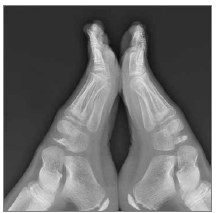

Es poco frecuente la bilateralidad, como se observa en la Figura 5, con diferentes estadios. El escafoides derecho muestra mayor fragmentación, pero menor esclerosis. En el escafoides izquierdo, se observa también fragmentación y mayor densidad (esclerosis en el fragmento proximal).

Figura 5.

Radiografía de perfil de ambos pies en un paciente con cambios morfológicos en ambos escafoides tarsianos. El derecho muestra mayor fragmentación y reabsorción que el izquierdo, pero menor esclerosis. El fragmento proximal del escafoides izquierdo muestra mayor densidad radiológica que el resto de las estructuras óseas secundaria a esclerosis.